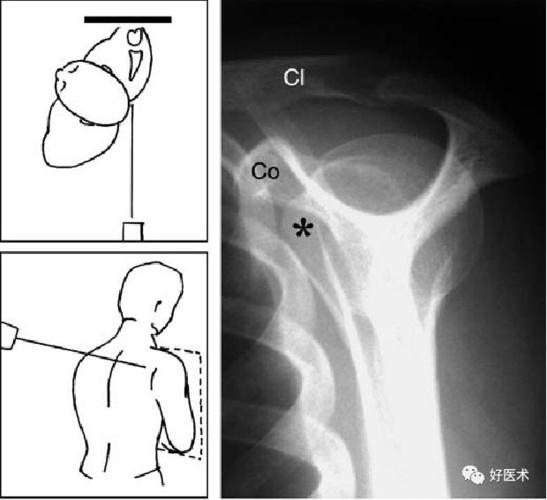

肩关节穿胸位x线摆位

肩关节穿胸位x线摆位,肩关节穿胸位x线图片

肩关节穿胸位标准片

肩关节穿胸位片

肩关节穿胸位

x线肩关节穿胸位拍法

肩关节穿胸位x线

肩关节穿胸侧位摆位

肩关节穿胸侧位

肩关节穿胸位示意图

肩关节穿胸位片图片